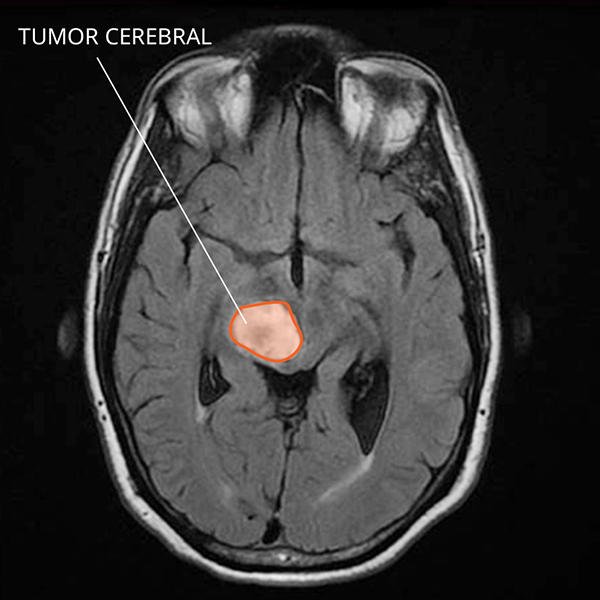

Imagen por resonancia magnética (IRM) de un glioma difuso de línea media en el cerebro.

¿Cómo se ve el glioma difuso de línea media en las imágenes por resonancia magnética?

El glioma difuso de línea media se suele ver como una masa diseminada en la parte central del cerebro. El contraste hace que algunas partes se vean más brillantes que otras. En los adultos, no es posible el diagnóstico del glioma difuso de línea media solo con imágenes porque los tumores se ven como los glioblastomas y otros cánceres de cerebro de grado alto.